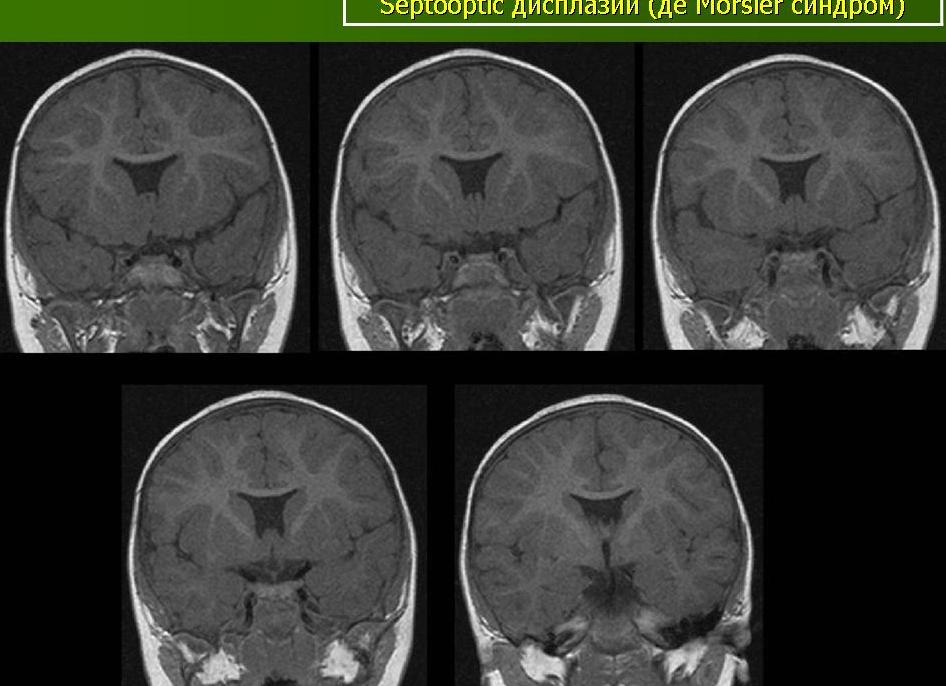

Синдромальные формы септо-оптической дисплазии. Помимо перечисленного, заболевание может проявляться с синдромом Айкарди. У этой патологии есть два клинических синдрома.